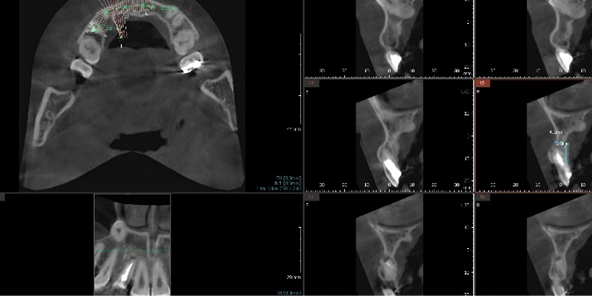

CT Precision Analysis & 3D Simulation

All preparations for surgery day are completed in advance during this phase.

• Precise analysis of alveolar bone and nerve location via CT scan

Precise analysis of

alveolar bone & nerve location via CT scan

• 3D analysis to determine implant placement position, angulation, and depth

3D analysis to determine

implant placement position, angulation & depth

• Patient-specific surgical guide fabrication

Patient-specific surgical guide fabrication

• Pre-fabrication of implant abutment and prosthesis

Pre-fabrication of implant abutment and prosthesis